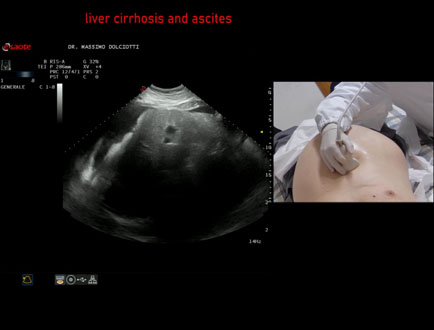

Data inserimento: 26/03/2026

Ecografia del: 17/03/2026

Strumento: Esaote MyLab Eight

Sonda: Convex Multifrequenza 1-8 MHz

Età Paziente: M 60 anni

Motivazione dell'esame: addome globoso, dispnea per piccoli sforzi, potus 1 litro di vino e birra, alvo con feci chiare, nicturia 1 volta.

Commento all'esame: le immagini ed il video documentano il fegato ad ecostruttura spiccatamente disomogenea, a profili irregolari, ridotto di volume e presenza di abbondante ascite.

Conclusioni: cirrosi epatica alcolica scompensata (decompensated alcoholic liver cirrhosis).